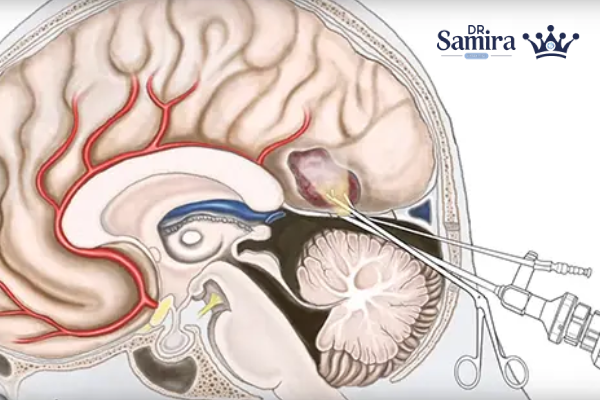

جراحی مغز

در اولین مرحله، جراحی مغز انجام میشود. هدف از جراحی، برداشتن حداکثری تومور است تا فشار از روی بافتهای مغزی کاهش یابد. در برخی بیماران بهدلیل موقعیت عمیق تومور، برداشتن کامل ممکن نیست، اما حتی کاهش حجم توده نیز در بهبود علائم مؤثر است. اگر تومور باعث انسداد جریان مایع مغزی شده باشد، پزشک ممکن است شنت مغزی قرار دهد تا فشار درون جمجمه کاهش پیدا کند.